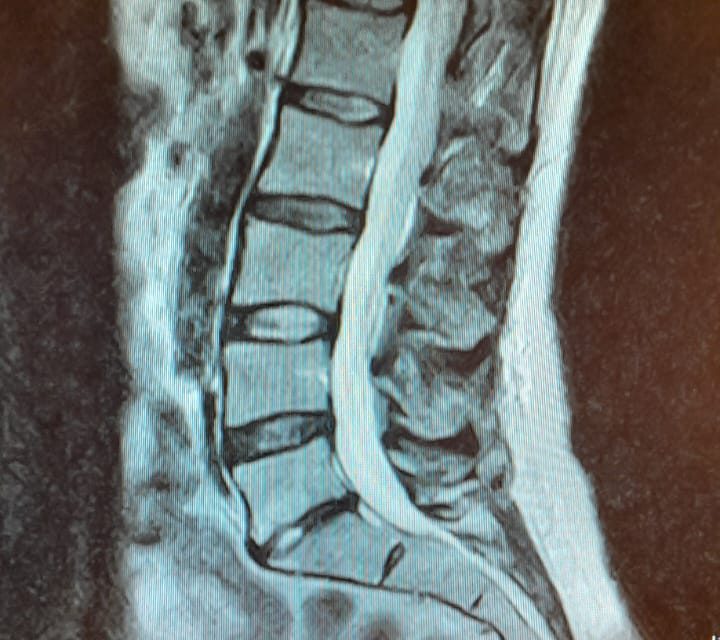

Marieta wordt geïnstrueerd door een ouwe strenge tang om op een wit bed te gaan liggen, dat vervolgens in een futuristische tunnel wordt geschoven. Dit is de MRI-scan van de rugpoli in Velp, die moet laten zien wat er aan de hand is met haar rug. Een halfuur lang hoort ze gezoem terwijl ze voor zich uit staart en afvraagt: “Waar heb ik last van?”.

Enkele weken later is Marieta opnieuw in Velp en hoort ze de resultaten van de MRI-scan. De tussenwervelschijven van haar rug zijn door overbelasting sterk verminderd. Die tussenwervelschijven zijn eigenlijk de kussentjes die je rug rechtop houden, een soort schokdempers.